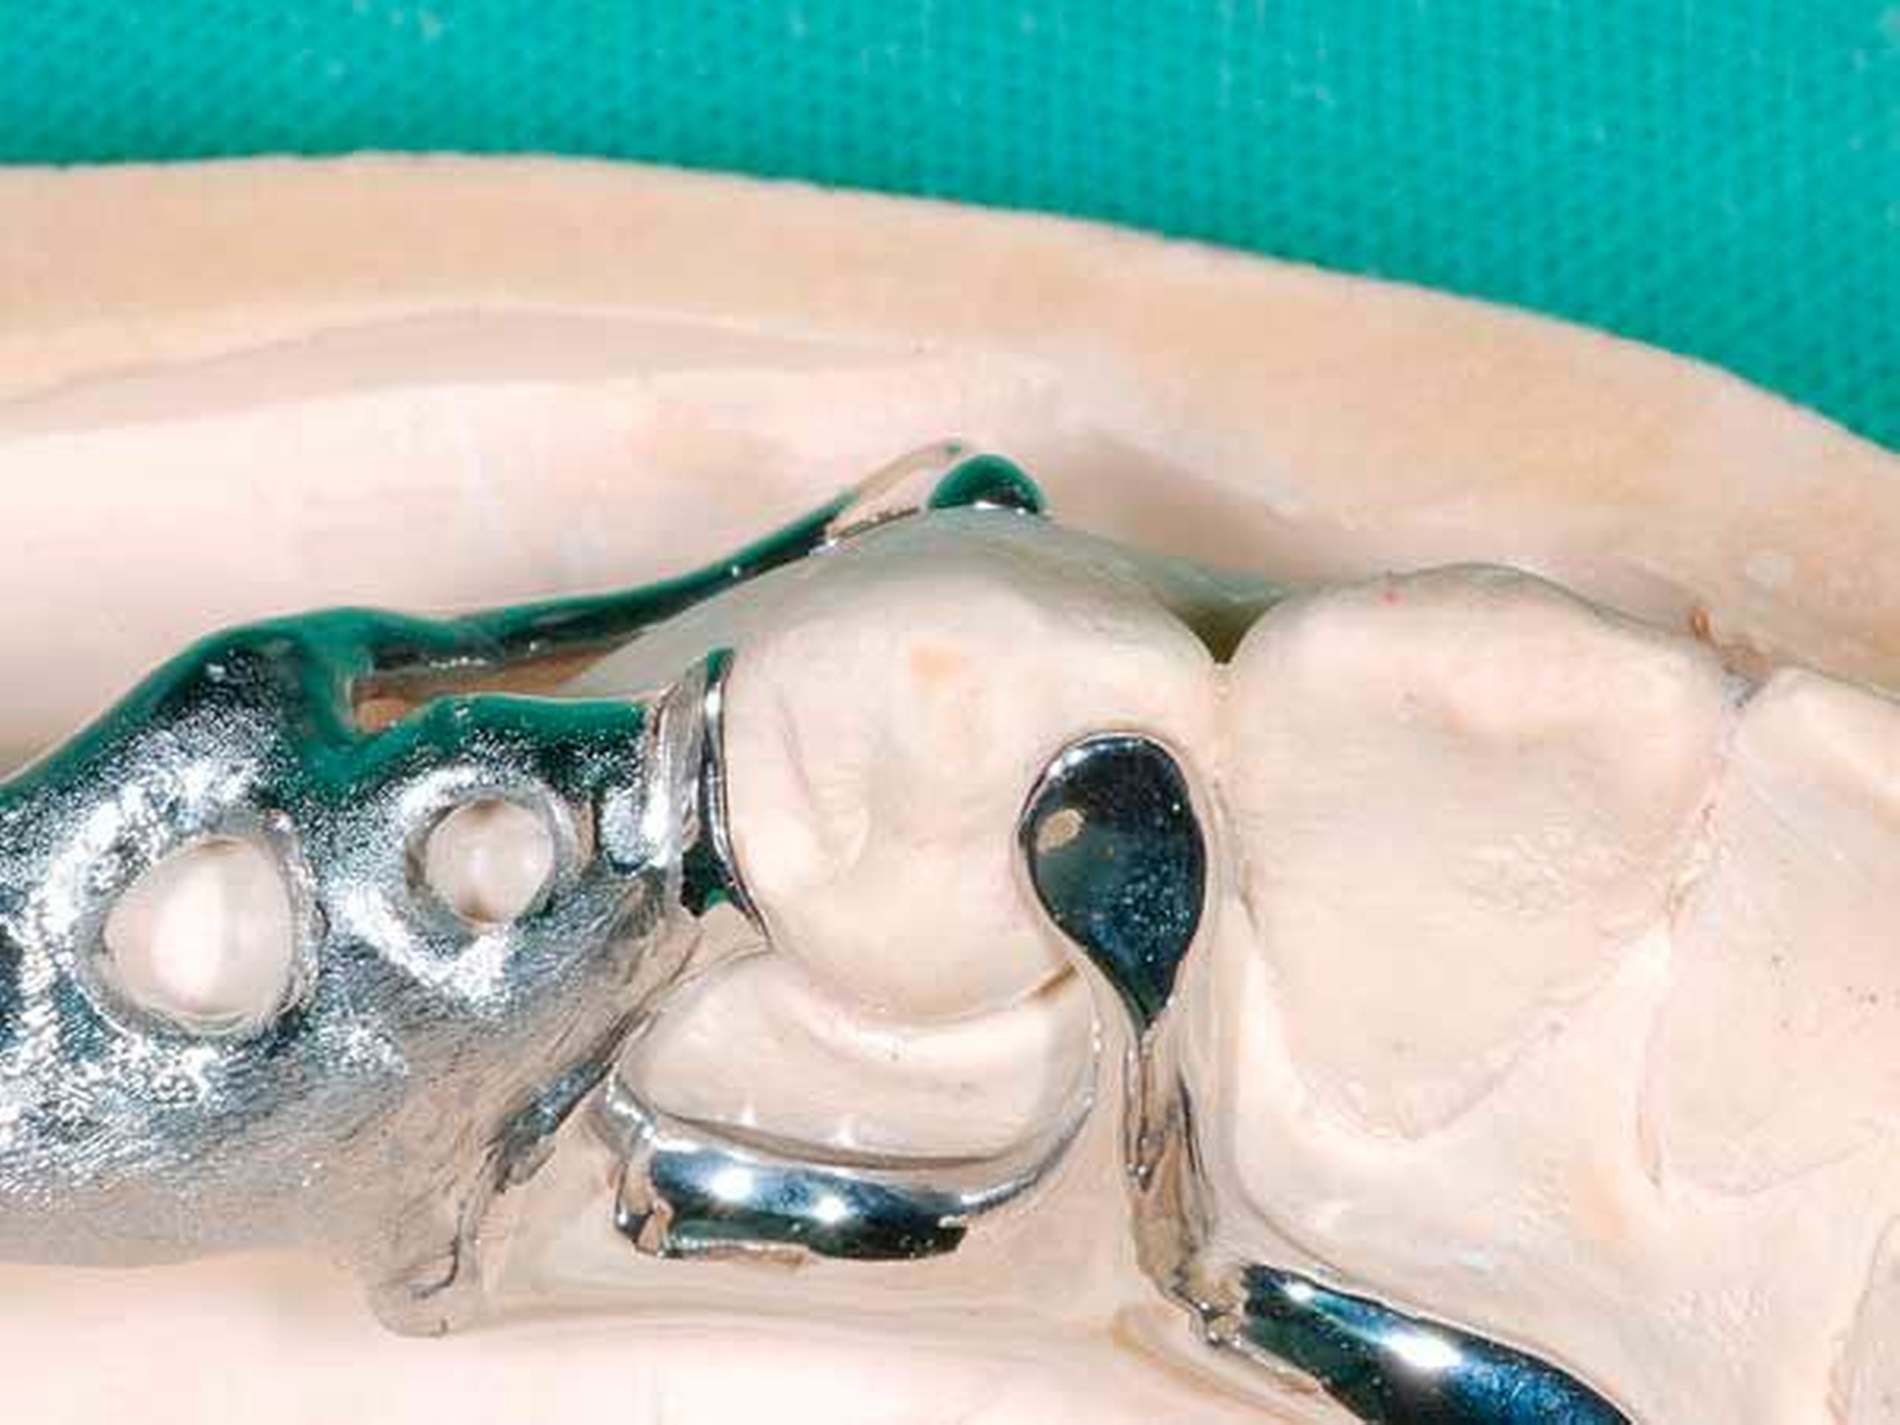

Die Patientin konnte mit einer Modellgussprothese und zwei RPI-Klammern an den Zähnen 34 und 45 erfolgreich versorgt werden (Abbildungen 3 und 4). RPI steht für Rest (meist sattelferne Abstützung), Proximal Plate (approximale Führungsfläche), l-bar (i-förmiger Retentionsteil). Das RPI-Klammersystem wurde 1963 von Kratochvil [Kratochvil, 1963] eingeführt und von Krol 1973 [Krol, 1973] weiterentwickelt. Das Klammersystem ist kein Exot. Es findet sich in nahezu allen internationalen Standardlehrbüchern der Prothetik und gilt als das mit am besten bewährte Klammersystem für die bilaterale Freiendsituation [Davenport et al., 1992; Krol, 1999; Carr et al., 2000].

Die proximale Platte der RPI-Klammer blockiert wirkungsvoll dislozierende Sattelbewegungen (Abbildung 5), der von gingival inserierende Retentionsarm ist nahezu unsichtbar. Aufgrund des langen Federweges ist der Retentionsarm praktisch ermüdungsfrei und lässt sich gegebenenfalls leicht aktivieren. Die Abstützung liegt sattelfern analog einer Back-Action-Klammer. Für die RPI-Klammer wird am Ankerzahn neben der üblichen mesialen Klammerauflage die disto-approximale Wand parallel zur Einschubrichtung im Schmelz präpariert (Abbildung 6). Die Präparation sollte mindestens 1 mm oberhalb der Papille enden. Die präparierte Fläche dient der flächigen Anlage der proximalen Platte (Abbildung 3).